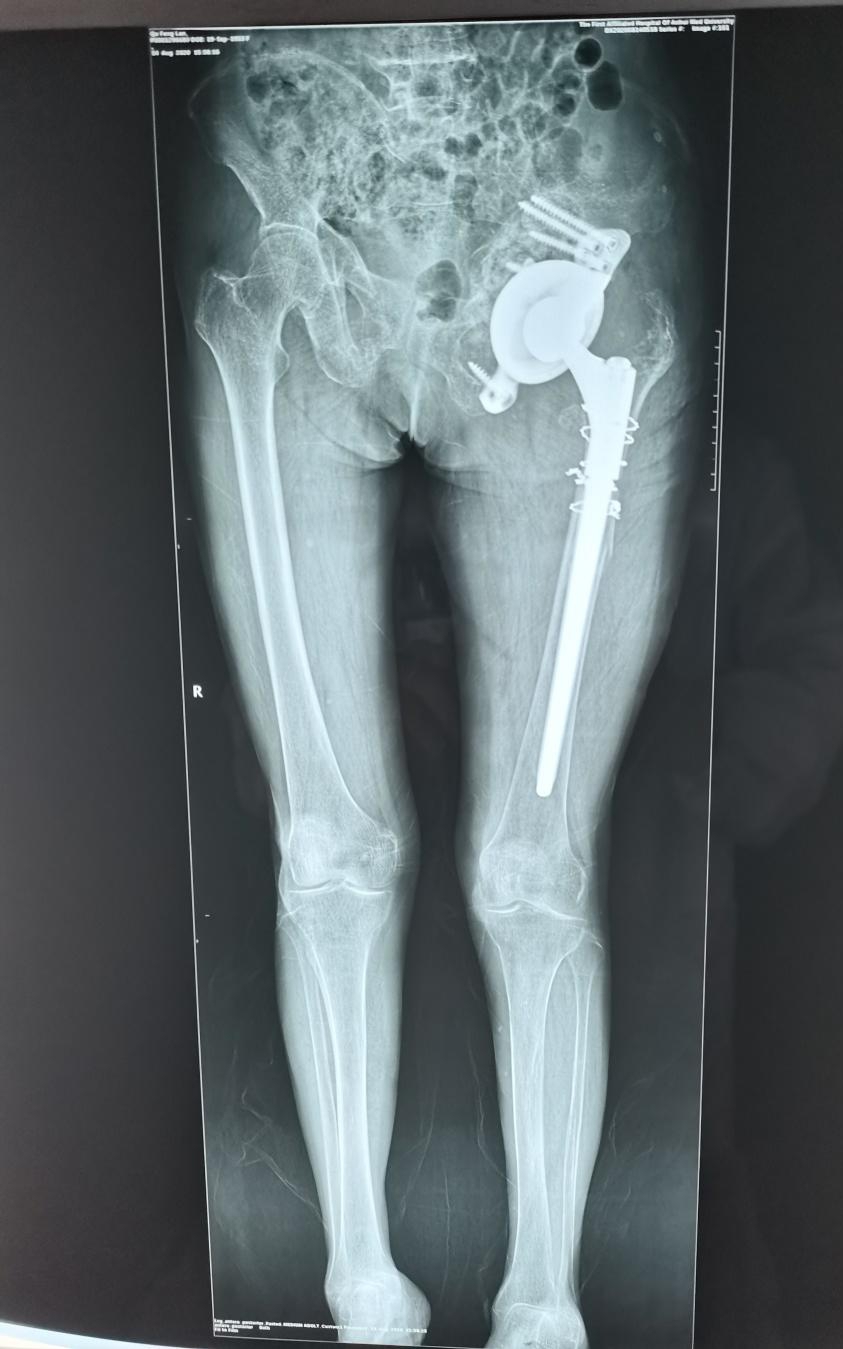

患者,瞿某某,女性,72岁。因“左侧髋关节疼痛伴活动受限1年”入院。该患者2006年因为股骨颈骨折在当地医院接受全髋关节置换手术。2016年因植入的假体无菌性松动接受了翻修手术。去年左侧髋关节再次出现疼痛,今年4月份症状明显加重,在当地医院摄片检查,发现假体再次松动。为求进一步诊治来到我院。

患者入院后经过详细的检查和评估后发现,因左侧髋关节接受过两次手术,原有的骨盆结构已经面目全非,存在巨大的骨缺损,利用常规的人工关节假体进行修复重建十分困难。关节外科团队在尹宗生教授的带领下为患者施行了翻修手术。利用3D打印技术联合国内的厂家进行技术研发,个性化地为患者量身设计了生物锁和髋臼假体。

手术过程中发现髋关节周围存在大量的原假体磨损碎屑,原髋关节处于脱位状态。髋臼假体连同原先的骨水泥均已经松动,股骨侧假体也松动了。当把原先所有的假体取出后,呈现在术野中的是一个直接通向盆腔的巨大窟窿。如果采用常规的髋关节置换假体是不可能填补如此巨大的骨缺损的。手术当中尹宗生教授仔细分离骨盆周围的重要结构,之后将预先打印好的髋臼假体安装在残缺不全的骨盆上,该假体正好能够匹配骨缺损。在预先设计预留的钉孔上置钉,并在髋臼底部植入了人工骨。手术共耗时3小时,术后患者康复满意,没有出现并发症,已顺利出院。